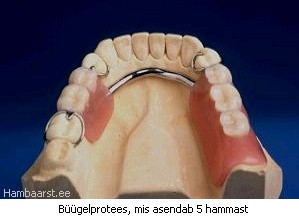

Juba moodustunud hambakivi eemaldamisega tegeleb hambaarst spetsiaalsete instrumentide abil.Kaugele arenenud igemepõletiku ehk parodontiidi raviks tuleb eemaldada selle põhjustajad. See tähendab, et hambaarstil tuleb lasta eemaldada hambakivi ja siluda hambajuurte pinnad takistamaks pisikute uuesti kinnitumist.

Harva ostub sügaval asetseva hambakivi eemaldamiseks ja igeme õige kuju taastamiseks vajalikuks kirurgiline operatsioon. |

Kui eespool toodud ravivõtted ei too oodatud tulemust või põletik ägeneb uuesti, võetakse appi konkreetsetele haigustekitajatele mõjuvad antibiootikumid. Kalli ja aeganõudva raviga on võimalik hävinud luu asemele kasvatada hambajuure ümber ka uut luud.